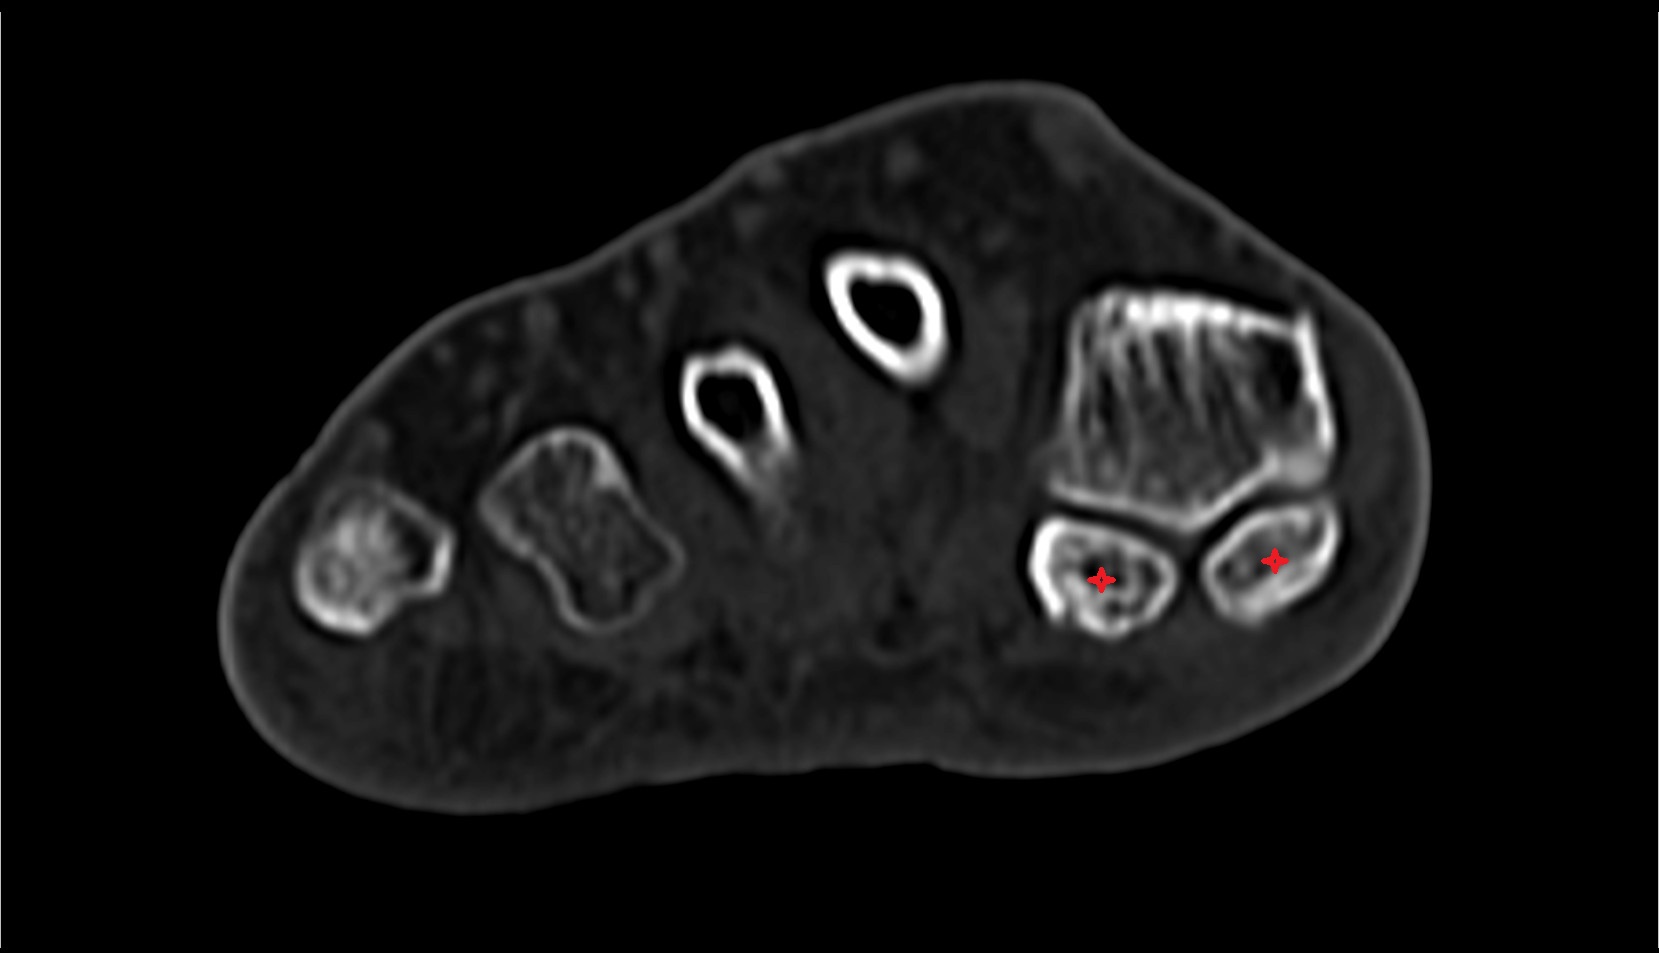

- Sesamoid bone of great toe

- Lateral sesamoid bone

- Medial sesamoid bone